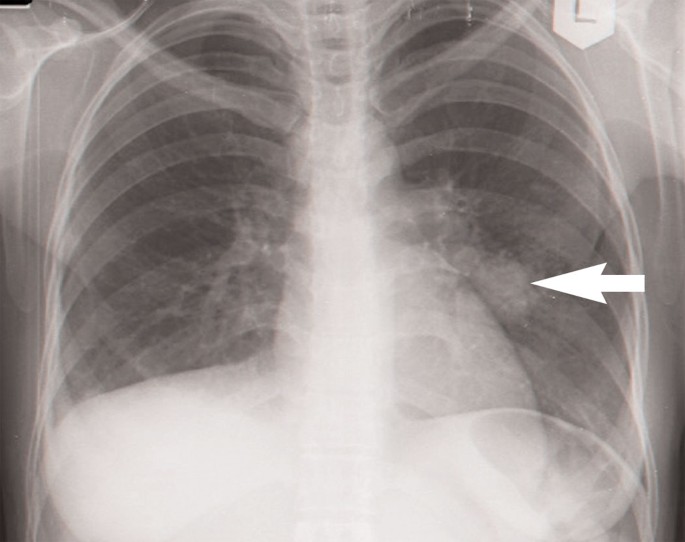

A 28-year-old recent immigrant from Ethiopia to Israel in her 26th week of pregnancy was examined for a persistent cough of three weeks duration with no fever and scant sputum production. She was in a good general condition, without tachypnoea, and had normal breath sounds. Her symptoms persisted and two weeks later a chest x-ray (CXR) showed a paracardial infiltrate in the left mid-lung field (Figure 1). Since she did not improve with antibiotic treatment, the possibility of TB was considered at her follow-up examination four weeks later. Since the regional TB centre was 60km away, she was referred to the local hospital and was admitted to an obstetric ward. On admission she was afebrile, not in acute distress, with a regular pulse of 104 and blood pressure of 110/66. There was no change in the finding in the CXR and her sputum was smear-negative for acid-fast bacilli. She was treated again with broad spectrum antibiotics and discharged after a week. Two weeks later she coughed up blood and was referred to the TB clinic. Considering her ethnic background, the persistent cough, haemoptysis, and the non-resolving pulmonary infiltrate, a clinical diagnosis of TB was made and treatment with isoniazid (INH), rifampicin (RIF), and ethambutol (EM) was begun. Later, her sputum culture returned positive for TB, sensitive to all first-line drugs.

The non-upper lobe location of the infiltrate was misleading; atypical lower lobe infiltrates, hilar lymphadenopathy, and pleural effusion may be found in primary pulmonary TB, particularly in HIV-positive patients where a miliary pattern is also more frequent.6